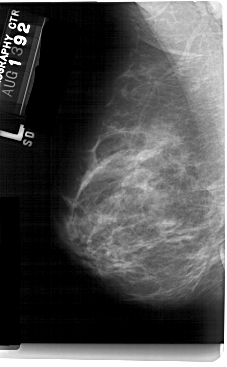

A_1434_1.LEFT_MLO

LEFT_MLO LINES 5491 PIXELS_PER_LINE 3391 BITS_PER_PIXEL 12 RESOLUTION 43.5 NON_OVERLAY